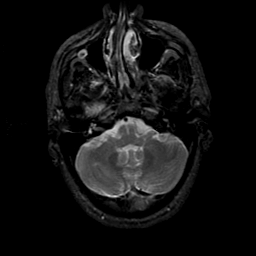

MR Study #21, November 3, 1991 -- Slice #10